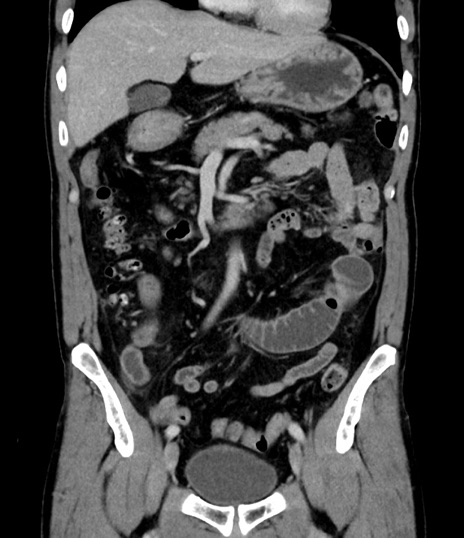

横断像